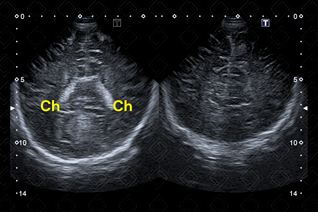

As imagens rotineiramente são obtidas nos planos coronal e sagital. As imagens coronais são obtidas colocando-se o transdutor transversamente pela fontanela anterior e angulando o feixe de ultrassom da frente para trás. As imagens sagitais são obtidas posicionando-se o transdutor em orientação longitudinal na fontanela anterior e angulando o feixe do meio para lateral (figuras 1 a 6).

Texto alternativo para a imagem Figura 1. Créditos: Dra. Elazir Mota - Rio de Janeiro/RJ

Texto alternativo para a imagem Figura 2. Créditos: Dra. Elazir Mota - Rio de Janeiro/RJ

Descrição das figuras 1 e 2: Ultrassonografia transfontanela cortes coronais, realizada varredura de anterior para posterior. CC – corpo caloso; Ch – plexo coroide; [cms-watermark] F – lobo frontal; N – núcleos da base; [cms-watermark] T – lobo temporal.